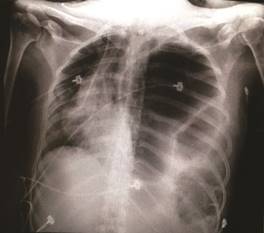

En el servicio de urgencias se solicitó radiografía de tórax portátil donde se identificó una gran imagen heterogénea que ocupaba en su totalidad el hemitórax izquierdo, el cual presentaba contornos lobulados, bien definidos, así como niveles hidroaéreos, con desplazamiento del mediastino y pérdida de los bordes del hemidiafragma izquierdo (figura 1). Se realizó diagnóstico de neumotórax espontáneo, motivo por el cual se colocó sello de agua endopleural. Sin embargo, ante la ausencia de expansión pulmonar, se solicitó tomografía axial computarizada (TAC) simple toracoabdominal. Diez horas después de su ingreso, la paciente presentó exacerbación de los síntomas respiratorios sin ameritar intubación orotraqueal, dada su evolución se interconsultó al servicio de cirugía general y al de imagenología.

Figura 1 Radiografía portátil de tórax. Se aprecia desplazamiento del mediastino con presencia de contenido abdominal en hemitórax izquierdo.

La radiografía de tórax sigue siendo un estudio inicial que aporta información básica para poder realizar el diagnóstico diferencial de un neumotórax, el cual se caracteriza por el aumento de la radiolucidez periférica (dependiente del volumen), visualización de los bordes de la pleura visceral que se dibuja como una línea radiopaca fina, y recordar que el desplazamiento del mediastino solo está presente en el neumotórax a tensión. En la radiografía de la paciente se presentó el desplazamiento del mediastino, ocasionado por el efecto de masa de las estructuras intraabdominales; además de que se alcanzan a delimitar imágenes compatibles con asas intestinales con niveles hidroaéreos que se confirman el corte sagital del Scout.